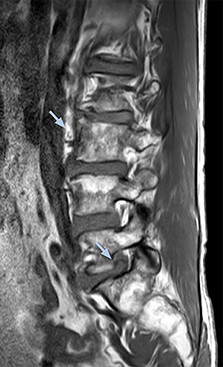

Distinguishing typical from atypical herniation informs the surgeon

“NerveVIEW is really useful for those cases where a nerve disorder is strongly suspected based on the clinical examination but our regular MRI images do not show any findings. These atypical herniations and spinal canal stenosis, occurring in 5% to 15% of the total lumbar herniation/stenosis cases are our main target when using NerveVIEW,” says Dr. Yabuki.

“Although symptoms of typical disc herniation and atypical hernia are very similar, the actual site of herniation is different. It is therefore important to characterize the nerve’s condition both inside and outside of the intervertebral foramina.

“Conversely, if we see no abnormality in NerveVIEW, we can assume at least that there is no severe condition that requires surgery. Like this, it can help us avoid unnecessary surgery. NerveVIEW can have a tremendous impact in this way.”